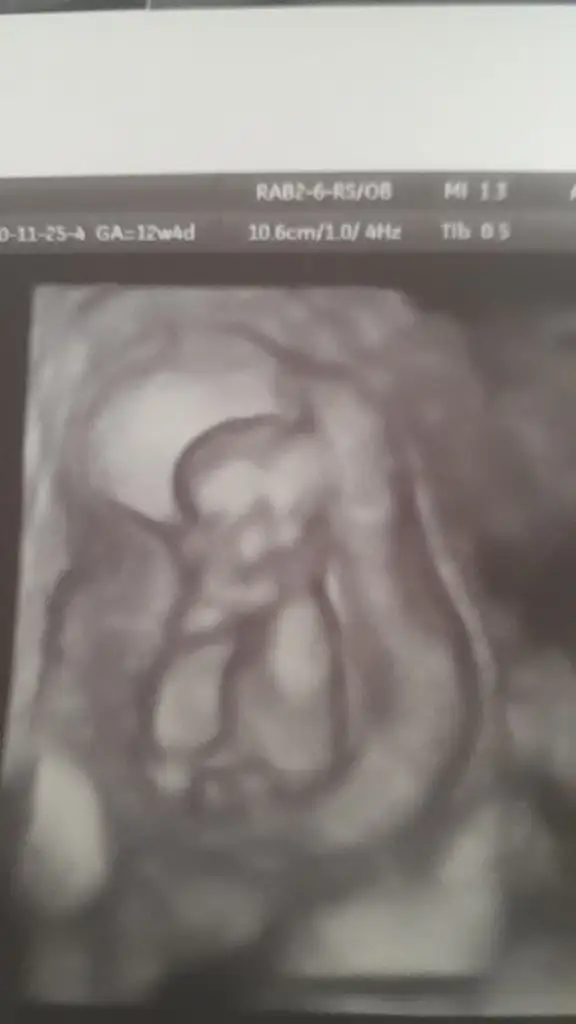

Evet dik gelmiş ama ucu tuhaf şekilde kırılıp düzlesmişNub erkek gorunuyor

Dr tahmin etmedimiEvet dik gelmiş ama ucu tuhaf şekilde kırılıp düzlesmiş

Pazartesi günü gideceğim, tahmin etmedi henüzDr tahmin etmedimi15+ olmudunuz

Kaç haftalık canım hiç net değil USG 11 12 13 haftalar olmalıCanim buna da bir bakar mısın?